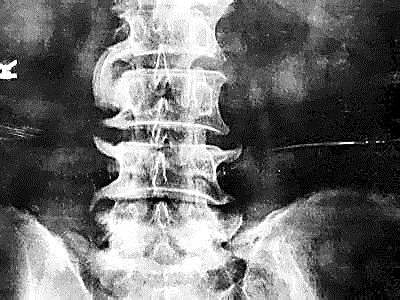

尤其是腰疼脖子疼膝盖疼,一拍片子,嘿!腰椎颈椎还真有骨刺,没准了,就是它了。再加上一些医术不精或别有用心的医生在旁边推波助澜的告诉患者,“你看,片子上有骨刺了,你的病就是这个骨刺引起的。但你不用担心,用了我的药就能让这骨刺消失。”

2、骨刺,只是X光片上看起来很尖,实际上并不是

是的,虽然X光片上看骨刺都是尖尖的,好像尖刀一样,但实际上,骨刺并不是尖的,而是钝的。

骨科医生在做手术时都会知道,那些在X光片上看起来尖尖的骨刺,在切开后会看到,其实骨刺表面包着一层圆润钝钝的软骨或结缔组织。只是这层圆润钝钝的软骨和结缔组织在X光片上不显示,只显示下面的骨头,所以尽管在片子上看骨刺好像是尖尖的,但是其表面其实是包着一层圆润的软骨的,并不会扎伤什么。